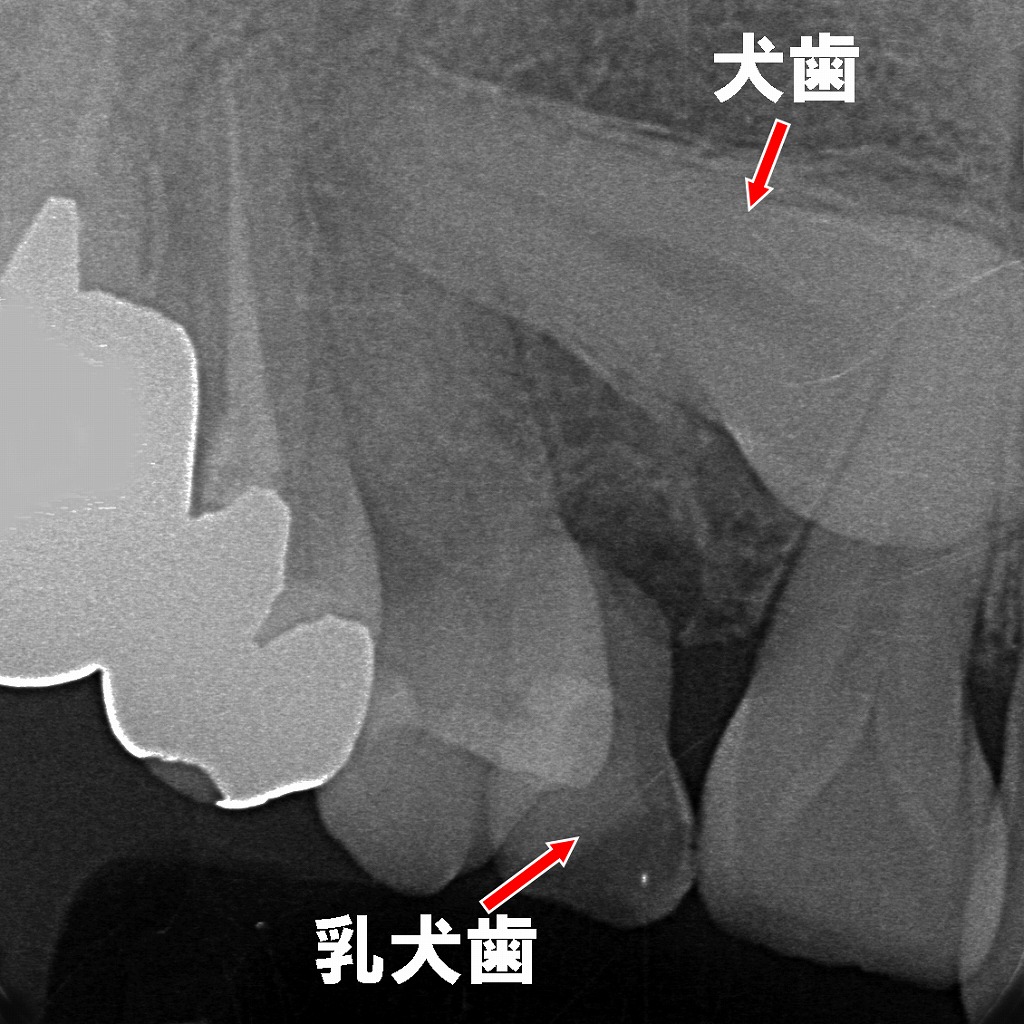

画像には、上顎犬歯(3番)の埋伏が認められ、赤い矢印がその位置を示しています。自然萌出が期待できない状態です。

■ 上顎3番の埋伏(Impacted Canine)

- 赤矢印の先に写る歯冠が、上顎犬歯の埋伏を示しています。

- 犬歯は萌出経路が長く、最も埋伏しやすい永久歯の一つです。

- 周囲の骨に厚く覆われており、自然萌出は困難です。

■ 歯肉切開・骨開削が必要となるケース

このように深く埋伏している場合は、

歯肉を切開 → 骨を一部開削(窓開け)して歯冠を露出させる処置が必要になります。

■ 矯正治療による牽引(エクストルージョン)

- 露出させた歯冠にボタンやブラケットを装着。

- マルチブラケット装置やワイヤーと連結して、犬歯を正しい位置まで牽引していきます。

- 周囲の永久歯(特に2番・4番)への根吸収のリスクにも注意しながら治療を進めます。

埋伏した永久犬歯が萌出方向を誤り、乳犬歯の根吸収が十分に進まず残存している状態。乳犬歯直下には永久犬歯が水平気味に位置しており、自然脱落しにくい典型的なパターンです。